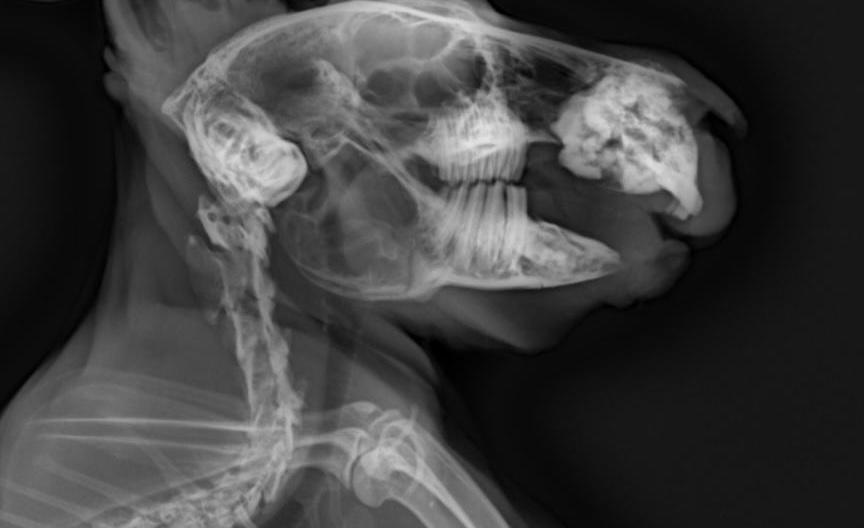

門牙感染、充滿膿液

牙根過長(食物太過多樣化、兔兔挑食誘發只食甜食,拒食硬草)

2. 影像檢查:X 光可評估腸道氣體、糞塊位置和牙齒結構;或需鎮靜。

• 牙科問題:在麻醉下修整牙齒,移除尖刺,或處理牙根膿腫。術後需服用止痛及抗生素。